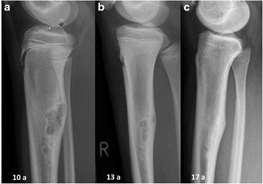

Other common cancers in children include lymphoma (cancer involving the lymph nodes), brain tumors, bone tumors, tumors of kidney or adrenal gland, soft tissue sarcomas, tumors involving the eyes, liver etc.